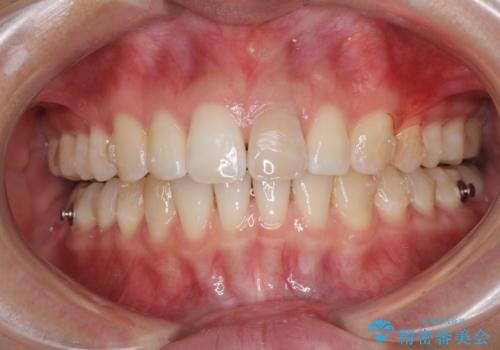

- 変色した前歯と突出した口元を気にして来院された患者様です。

口元の突出感はインビザラインにより歯列を整え、その後に、前歯をオーダーメイドタイプのオールセラミッククラウンにて補綴治療することとしました。

長時間のマウスピース装着と、患者様自身でのゴムかけに協力いただき、口元の突出感をしっかりと改善することができました。

前歯のオールセラミッククラウンもまるで本物の歯のように仕上がり、患者様には大変満足していただきました。